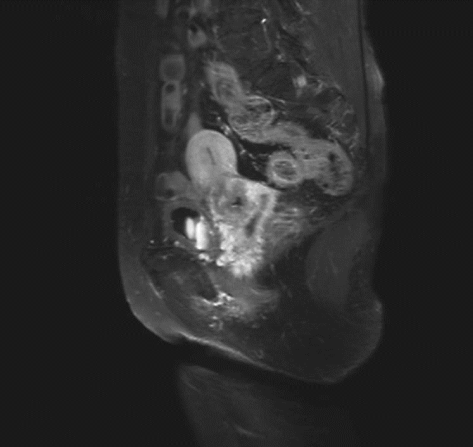

ⅠB1期宫颈癌MR ⅠB2期宫颈癌MR

ⅡA1期宫颈癌MR ⅡA2期宫颈癌MR

ⅡB期宫颈癌MR ⅢA期宫颈癌MR

ⅢB期宫颈癌MR ⅣB期宫颈癌MR